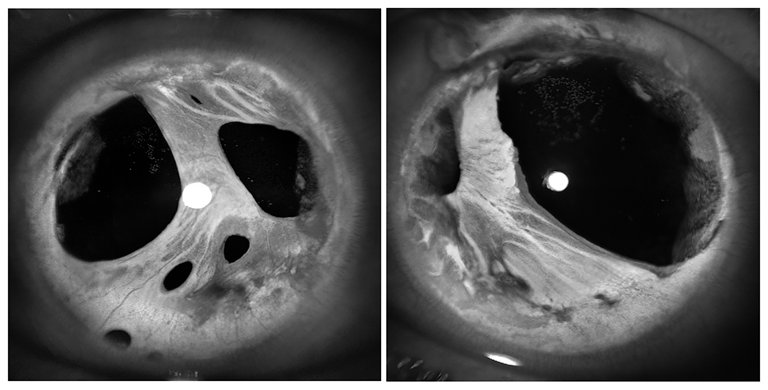

Axenfeld-Rieger Syndrome

Presented by Sean Grout, OCT-CThis photograph received 2nd Place in the category "Monochromatic Photography" and was displayed at the 2024 ASCRS/OPS Society Exhibit.